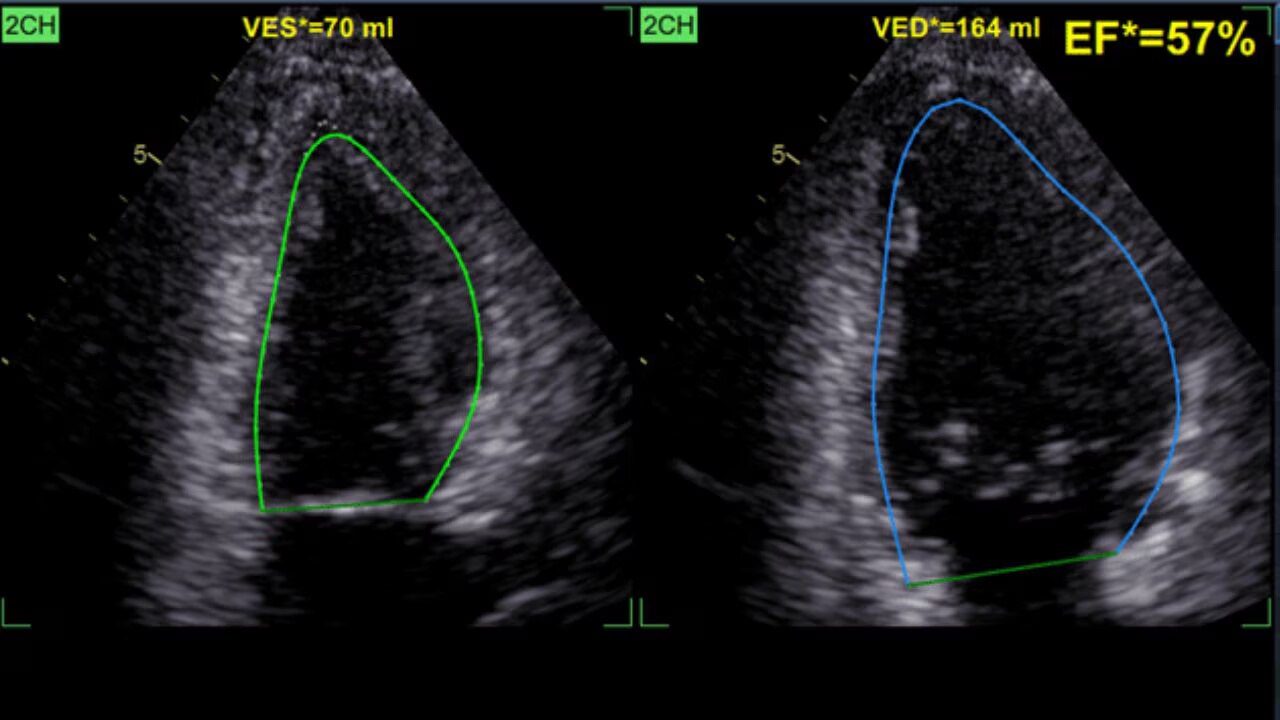

Our latest AI-based technologies can help improve workflow efficiency

The new Vivid T series ultrasound systems have been designed to meet today’s challenges. To allow more quality time with patients, increase diagnostic confidence, and reduce inter-operator variability - all at a price point accessible for private practices.

The Vivid T series cardiovascular ultrasound has been designed to meet today’s challenges. The Vivid T series allows more quality time with patients, increases diagnostic confidence, and reduces inter-operator variability - all at a price point accessible for private practices.

"The Vivid T9 Ultra Edition AI-based automated measurements help my staff complete a standard echo exam faster, and with less variability. The new Penetration button on the touch screen helps give the sonographers the extra boost we often need with challenging imaging windows. As a busy private cardiology practice, we appreciate having these advanced options available on an affordable cardiovascular ultrasound system.”